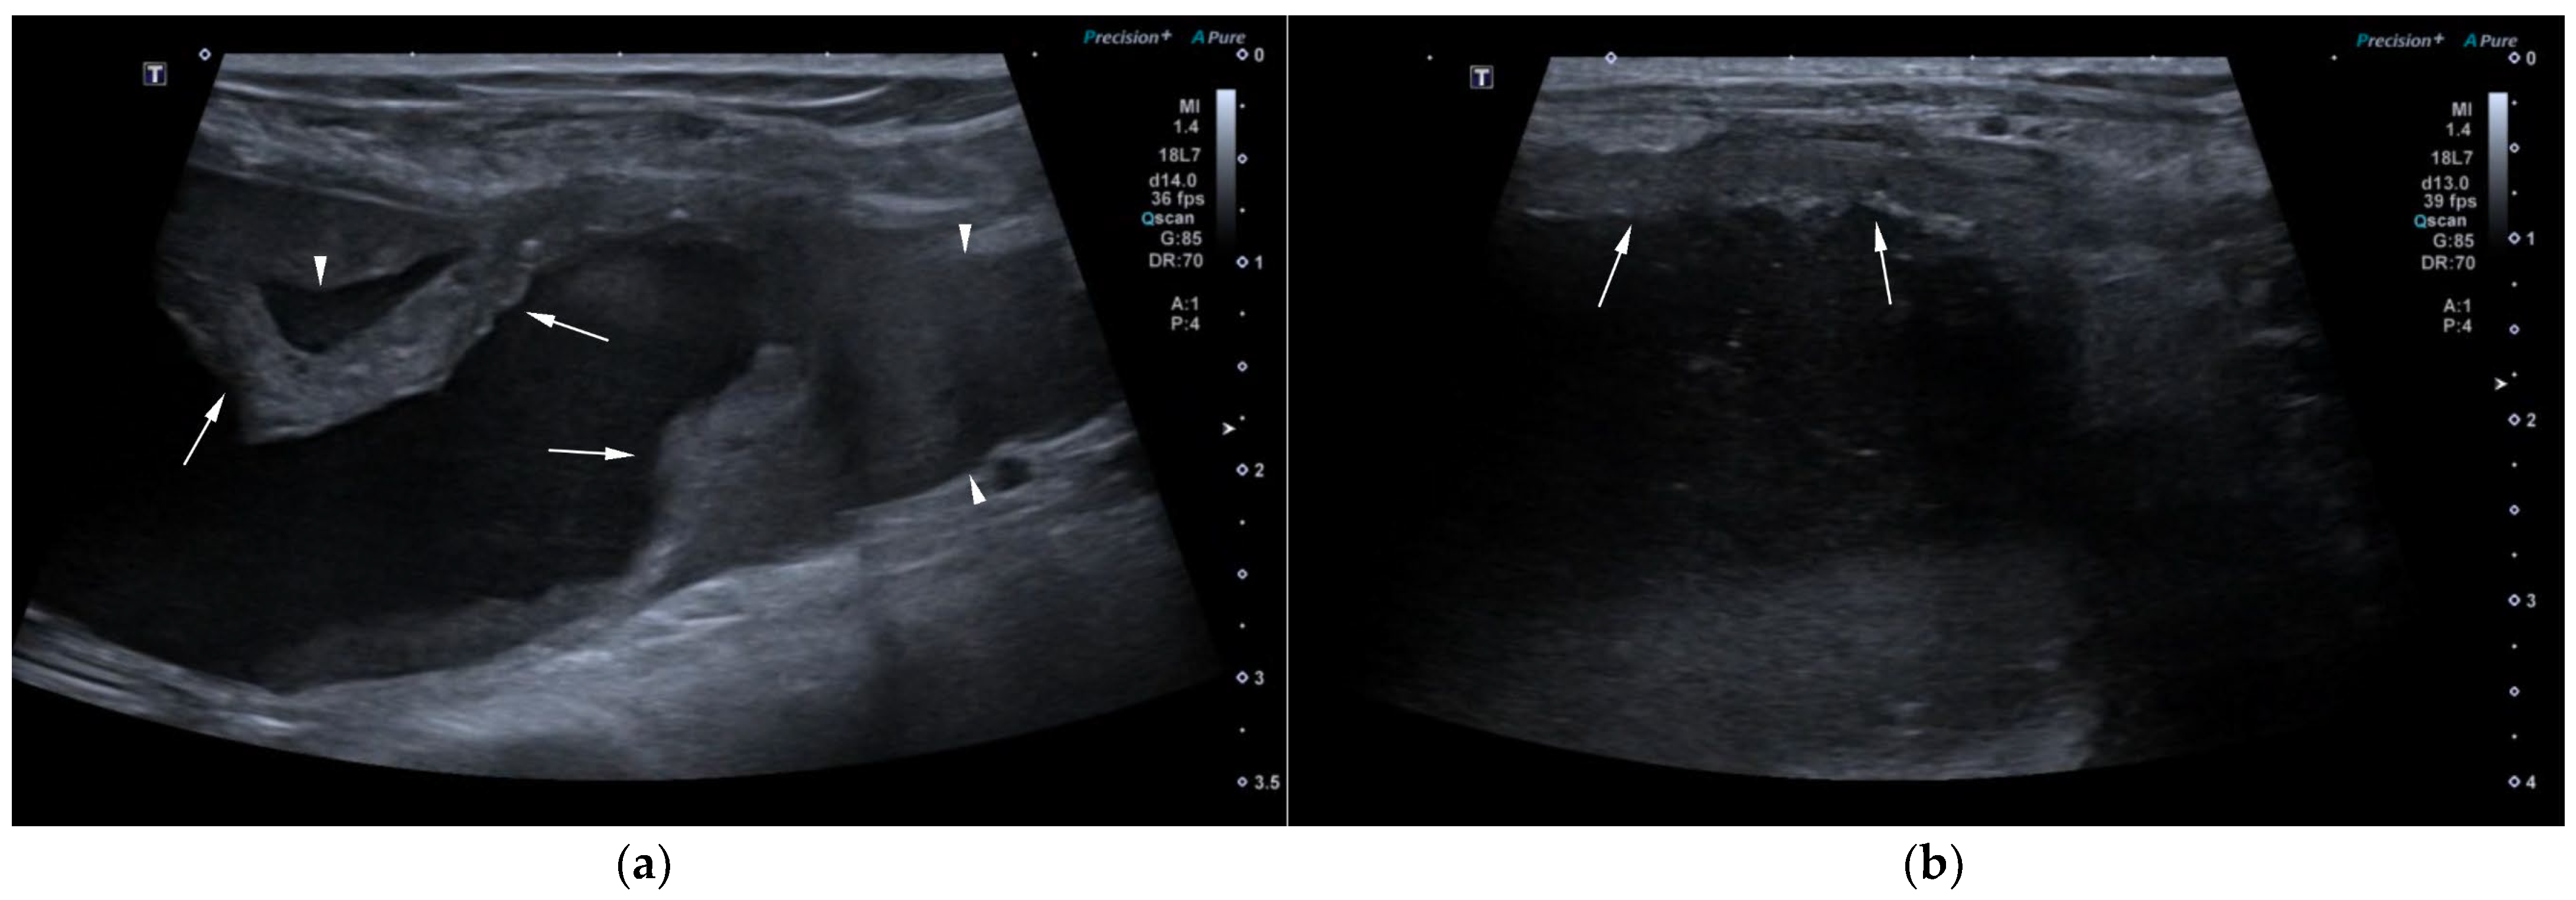

AUS in all three dogs revealed a fluid-filled cavitary structure originating in the caudal peritoneum between the colon and urinary bladder and extending cranially through the mid-abdomen, causing a mass effect. In cases 1 and 2, the lesion continued bilaterally as paired, thin tubular extensions coursing caudally through the inguinal rings adjacent to each testis (Figure 1a). In case 1, a focal mural narrowing resembling a uterine cervix was noted caudally (Figure 1b). The wall was thin and smooth in case 1, while in case 2 it was irregular, especially in its caudal aspect (Figure 2a,b). No information was available regarding the course of the UM horns or wall appearance for case 3. The luminal content consisted of echogenic, inhomogeneous fluid in all cases (Figure 3a); in case 2, sedimentation created fluid–fluid levels (Figure 3b).

Additional findings in all dogs included: enlarged, heterogeneous, cystic prostate; echogenic sediment in the urinary bladder; free peritoneal fluid [moderate and echogenic in case 2 (Figure 2a); mild and anechoic in cases 1 and 3]; and bilateral medial iliac lymphadenomegaly (moderate in cases 2 and 3; mild in case 1).

Figure 2. AUS of case 2: (a) Longitudinal view of the caudal UM, showing irregular wall margins (arrows), intraluminal inhomogeneous fluid, and free echogenic peritoneal fluid (arrowheads); (b) Detailed view of the UM wall demonstrating luminal irregular margins (arrows).

Figure 3. (a) AUS of case 1; transverse view of the most dilated UM segment containing inhomogeneous echogenic fluid; (b) AUS of case 2; oblique view showing two sections of the UM containing a moderate volume of sedimented material (asterisks), creating marked fluid–fluid levels.